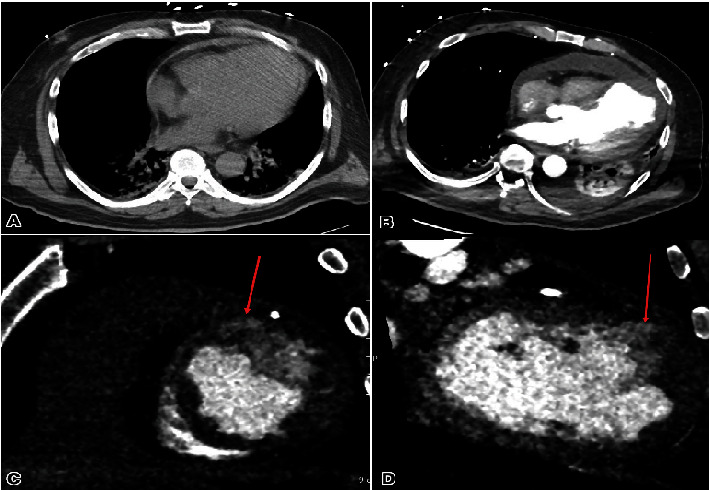

心室壁破裂与急性心肌梗死后的不良预后有关。我们描述了一例经皮冠状动脉介入治疗后心肌梗死心尖壁破裂的病例。我们的病例强调了迅速评估、诊断和处理的重要性,以提高面临这种危急情况的患者的存活率。

Ventricular wall rupture is associated with poor outcomes subsequent to an acute myocardial infarction. We describe a case of postmyocardial infarction apical wall rupture following percutaneous coronary intervention. Our case emphasizes the importance of swift evaluation, diagnosis, and management to enhance survival in individuals confronting this critical condition.